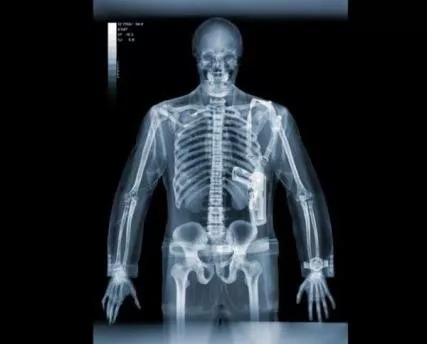

1.X射线+建模:

对于枪杀或无法判别身份的尸体,法医会使用X光机,确定死者骨骼畸形情况以及子弹和其他物体的位置,并且紫外线可帮助他们探测脑部残余。

在现场数学分析技术的帮助下可以立体 ,平面、直观地再现 ,来观察尸体系统性的病理改变征象。

人体X光片显示图(图片来源:家庭医生论坛)